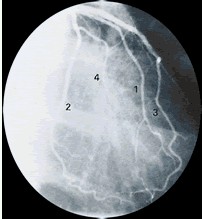

前/后位:左冠状动脉 |

1.第一边缘支 2.回旋支 3.冠状动脉左前降支 4.边缘支因脊柱和胸骨的重叠,前后位很少用。 |